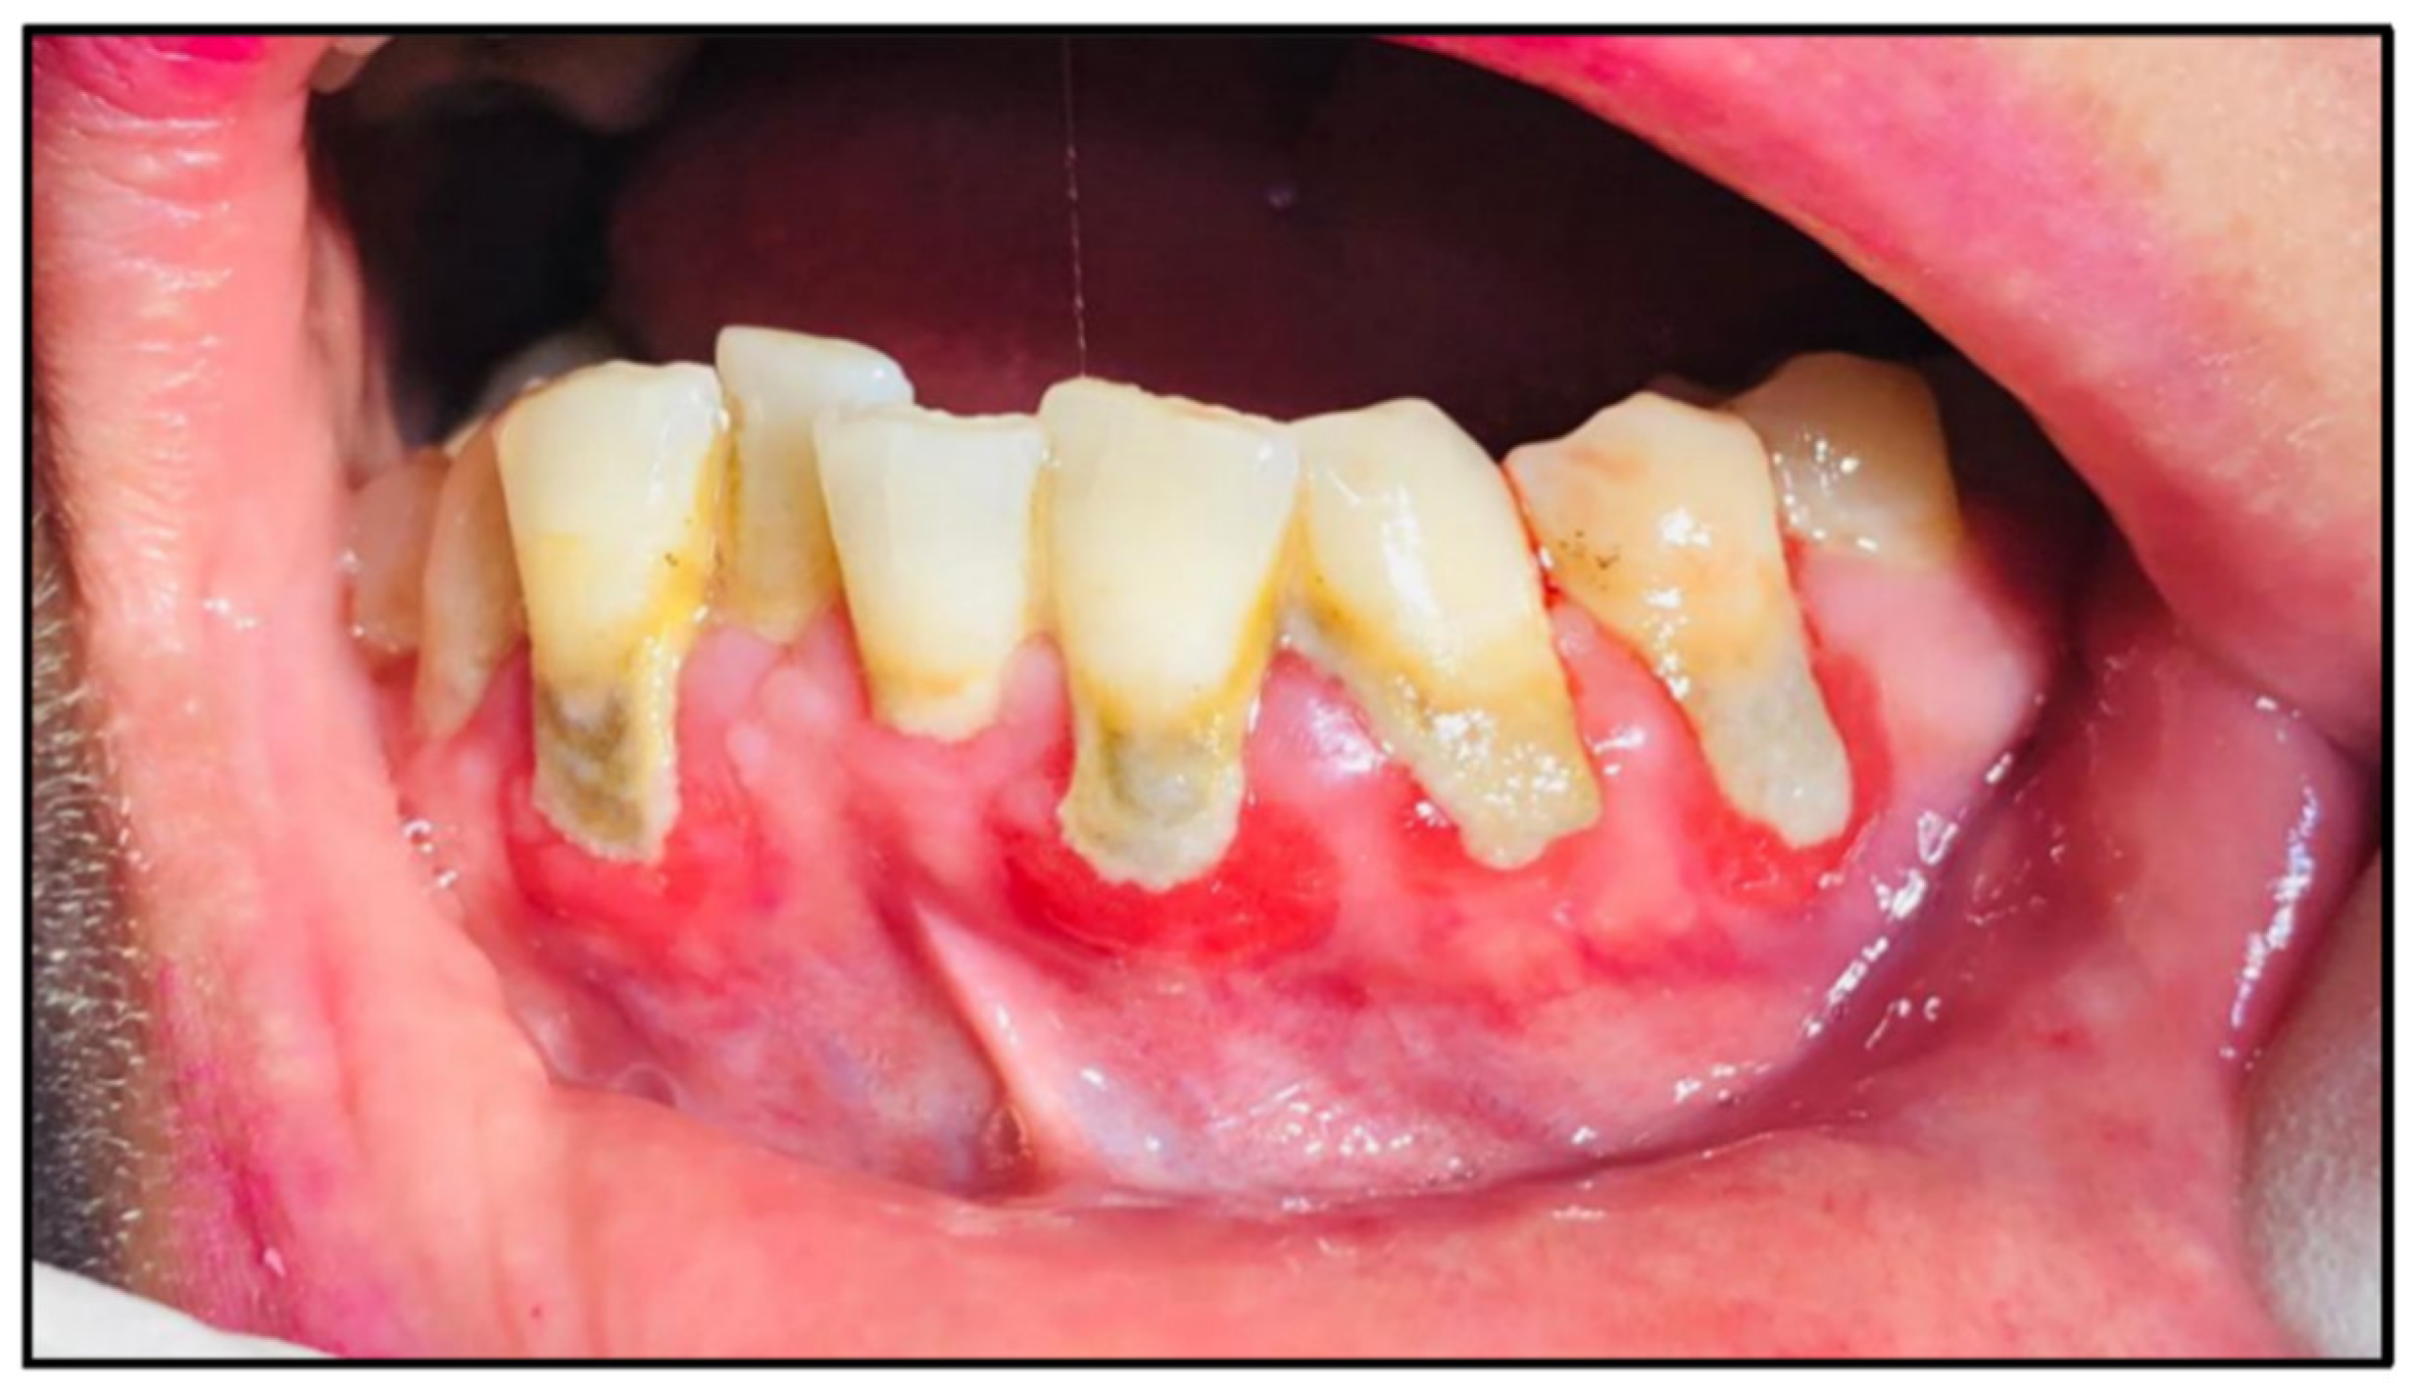

Periodontitis is a frequent chronic inflammatory illness caused by a collection of bacterial plaque in the subgingival area [13]. It is characterised by progressive damage to the periodontal and tooth-supporting tissues (Figure 2), which may lead to the loss of teeth [9,14]. Periodontitis can clinically be manifested as pain, loss of periodontal supporting tissue, presence of periodontal pockets, and gingival bleeding [15,16]. If untreated before RT, periodontitis may lead to acute or chronic complications in the patients during RT [17]. Periodontitis can be a trigger for the incidence of osteoradionecrosis [9]. Also, if accompanied by poor oral hygiene, periodontitis can lead to mucositis [18]. It was hypothesised that periodontitis in HNC patients is related to the dysregulation of the inflammatory response of the mouth that results from RT. Furthermore, RT-related hyposalivation and oral microbiome changes are other explanations for the incidence of periodontitis in HNC patients [9,19]. Periodontitis may be prevented by maintaining proper oral hygiene with frequent dentist visits [20]. Extraction (before RT initiation) of any defective tooth that is expected to require future surgical intervention [9], and the use of probiotics together with scaling and root planning [21]. The treatment options for periodontitis include antimicrobial mouth rinses to control bacterial development and minimise periodontal inflammation [22], which has a potential role in wound healing, and periodontal surgery (such as flap surgery, bone grafts, guided tissue regeneration, and gum grafts) may be required in cases where non-surgical methods are not enough [23].

Figure 2.

Periodontitis (redness with gingivitis in the internal surfaces of the gingiva) in a female HNC patient after RT completion.